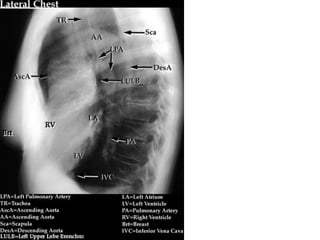

• On the lateral

radiograph

• drawing an imaginary

line anterior to the

trachea and

posteriorly to the

inferior vena cava.

• The middle and

posterior

compartments can be

separated by an

imaginary line passing

1 cm posteriorly to the

anterior border of the

vertebral bodies.